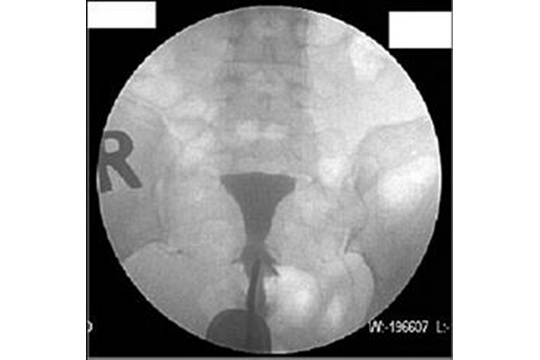

相信不少準備孕育下一代的夫妻都曾聽說過:一對夫婦若有正常性生活超過1年而未能自然成孕,已可界定為不育。但大家可知道不育的常見成因有哪一些?原來有3成不孕個案是由女方輸卵管阻塞造成;有2成是排卵障礙,如月經不正常、排卵不順甚或不排卵;另外3成則是男方精子稀少、活動力不佳等問題。就輸卵管阻塞問題,曾有女生從網上聽說輸卵管攝影會很痛,於是逃避就診,殊不知一些不孕婦女只需經由輸卵管攝影檢查,就能疏通輕微阻塞,解決多年不孕的困擾,成功得子。因此不孕夫妻應及早勇敢就醫。